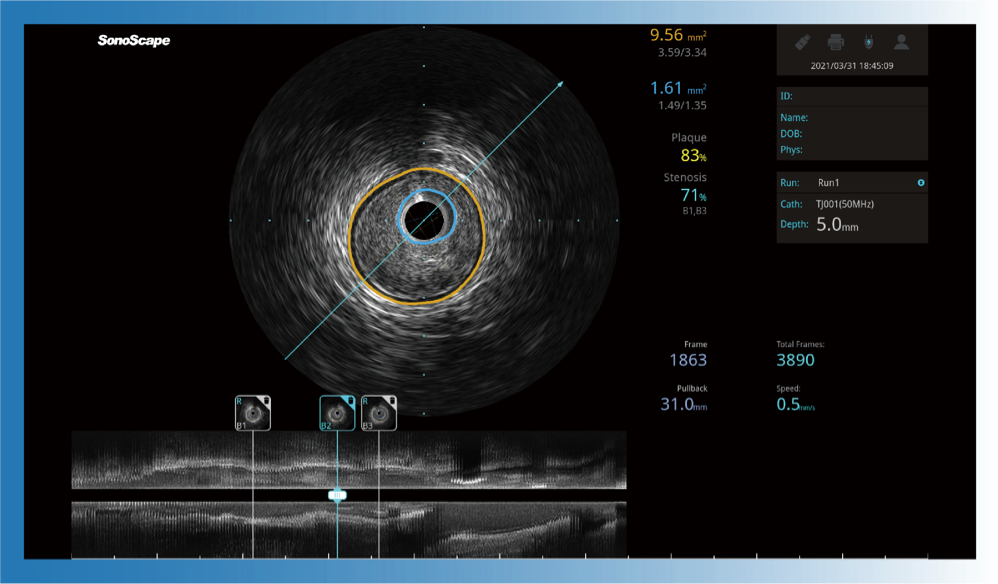

1xBET宽频IVUS图像

传统IVUS图像

对比传统IVUS导管成像,1xBET宽频IVUS图像的近场支架梁显影更细腻,远场中膜外血管仍清晰可辨,兼顾远中近,兼顾分辨力与穿透深度

一键智能描迹,自动测量斑块负荷、面积狭窄率等指标,准确率高于90%